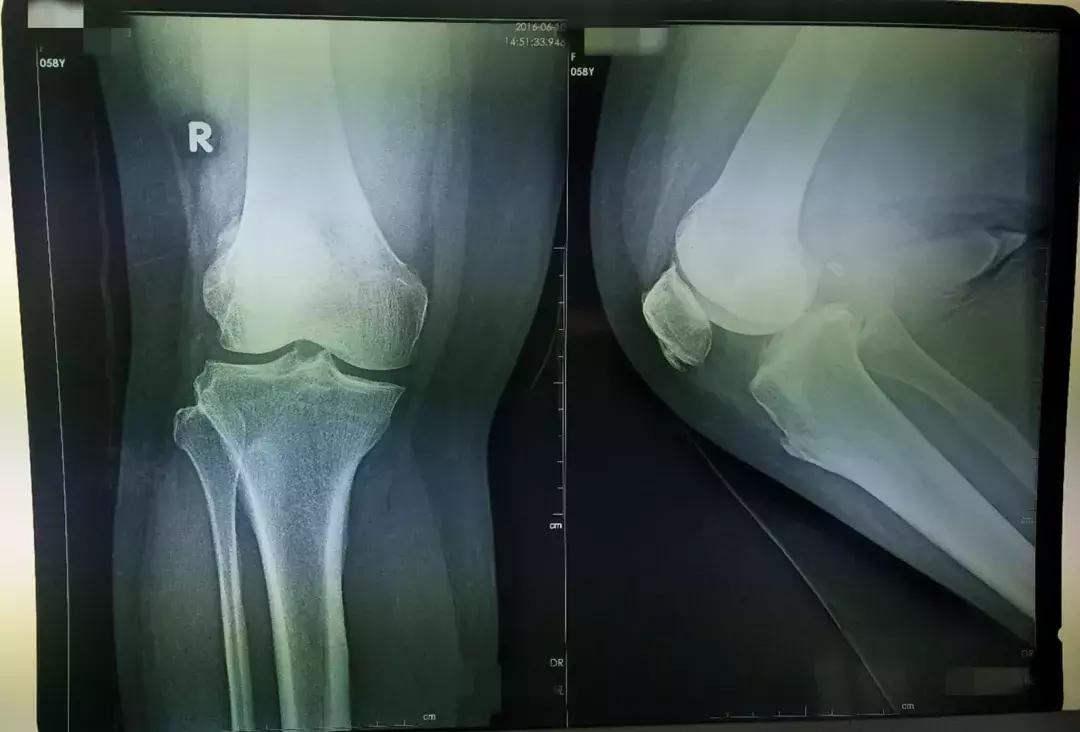

患者是一名中老年女性,患有严重的膝关节退变性骨关节炎,右膝关节明显内翻畸形,膝关节内侧疼痛伴明显活动受限,影响日常生活,曾就诊于省内多家医院,中药西药吃了一大堆,关节内还注射了润滑剂,采取保守治疗效果不佳,很多医院都建议进行关节置换。在得知张云海博士坐诊的消息后,患者抱着很大的希望前来就诊,经过查看病历、X线片、CT片,为改善患者症状,提高患者生活质量,并考虑到患者有强烈的保膝意愿,张云海博士建议患者进行HTO手术治疗。

患者入院后,骨科医护人员根据患者身体症状,完善相关检查,在张云海博士的指导下,邱生海主任及闫煜军主管医师制定了精确而详细的手术方案及术后康复方案。25日,张云海博士为患者实施了HTO手术,骨科医护人员全程配合,手术用时2小时50分,进行顺利。矫正了患者膝关节内翻畸形,恢复了关节的正常力线及功能,缓解了疼痛症状。